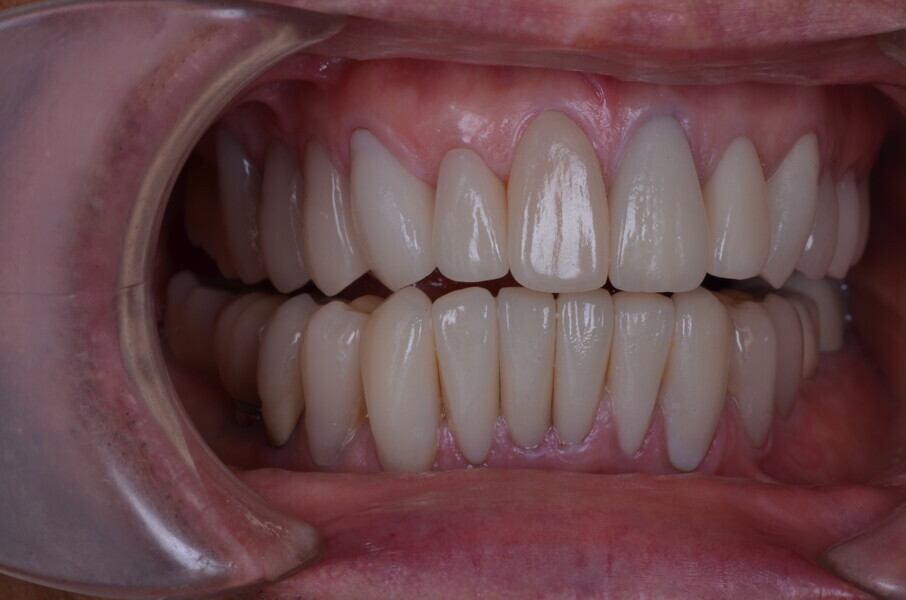

Figure 26 Closed mouth post op